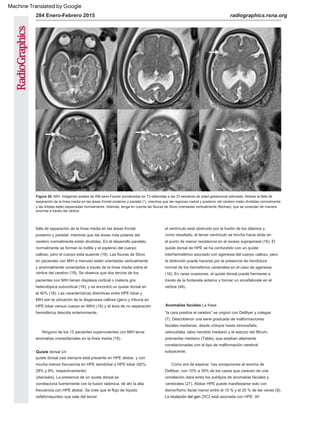

Figura 7. Alobar HPE. (a) La imagen de US axial oblicua obtenida a las 18 semanas muestra tálamos fusionados

(puntas de flecha) y un monoventrículo (*). (b) La ecografía axial oblicua obtenida a un nivel más alto muestra la

morfología en forma de copa de los hemisferios no hendidos (flechas) "ahuecando" el monoventrículo (*).

Figura 11. Alobar HPE. La imagen de RM fetal axial muestra un

único monoventrículo primitivo (*) rodeado de tejido cerebral

anormal. Esto se describe como el cerebro "en forma de bola".

Figura 8. Alobar HPE. La imagen de RM fetal coronal muestra un

monoventrículo (punta de flecha), hipotelorismo (flechas negras)

y una hendidura facial en la línea media (flecha blanca).

Aq = acueducto de Silvio, H = hipocampo, T = partes de tálamos

en forma de mancuerna (etiquetados por neuropatholo gist).

(Reimpreso, con autorización, de Amirsys.)

Figura 9. Alobar HPE. Imagen de RM fetal sagital que muestra un

gran “quiste dorsal” (puntas de flecha) y una morfología de “copa”

del cerebro (flecha). Obsérvese el perfil fetal normal en este caso.

Alobar HPE no siempre se asocia con facies dismórfica.

Figura 10. Alobar HPE. La vista de la autopsia fetal desde arriba

del cerebro muestra una morfología de "copa" del manto cerebral

sin división en hemisferios. El quiste dorsal desinflado se refleja

en la mitad de la bóveda del cráneo bivalvo.